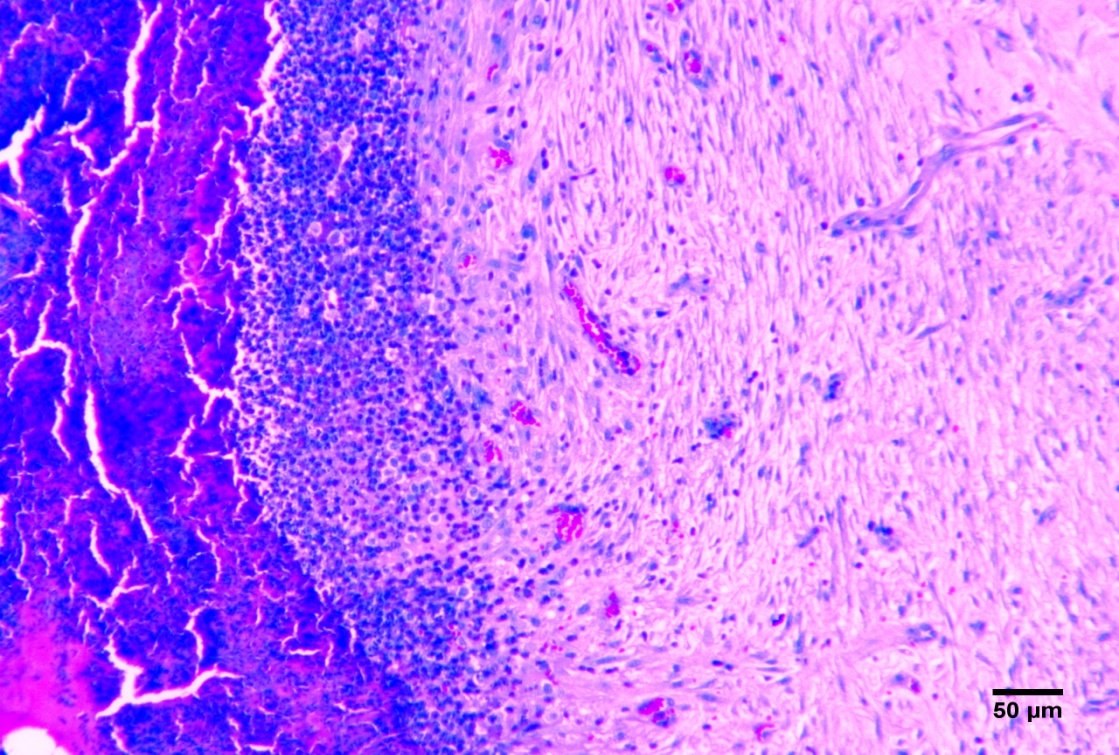

O presente estudo teve por objetivo desenvolver e investigar experimentalmente as potencialidades de aplicação de bioadesivo a base de amido aditivado, como sistema patches transdérmico e intradérmico epitelial, em formato de filme monolaminar tubular, visando à ação futura para administração de anti-inflamatórios, antimicrobianos e atuação terapêutica. Foram utilizados 20 coelhos machos e fêmeas, da raça Nova Zelândia, adultos, separados em quatro grupos com cinco animais que passaram por cirurgia para realização de defeito dérmico. O grupo GA e o grupo GB (controle dérmico e intradérmico negativos respectivamente) não receberam biomaterial na ferida. Os animais do grupo GC receberam o biofilme adesivo de forma dérmica que foi suturado sobre a ferida e o grupo GD, recebeu o biofilme adesivo de forma intradérmica. Aos sete e 14 dias de pós-operatório os animais foram anestesiados novamente para criação do defeito para biópsia. A análise estatística da planimetria foi conduzida a partir da média dos grupos, utilizando-se o teste de Tukey a significância de 1%, através do software computacional estatístico SAS®. A pesquisa demonstrou que o biofilme utilizado até sete dias reduz o processo inflamatório e estimula a neoangiogênse.